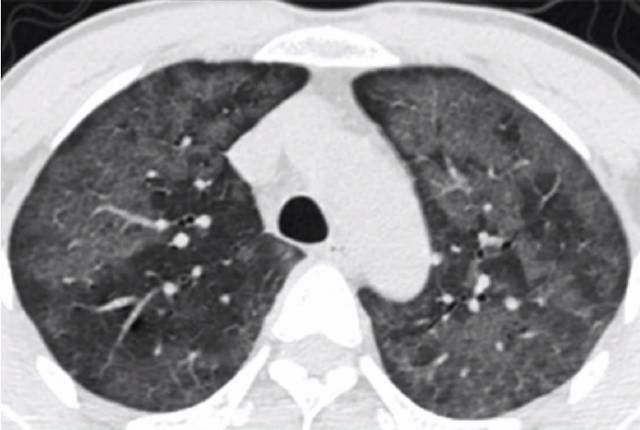

男,46岁,弥漫性GGO,双肺都是单片密度增高,呈半透明状,可见血管穿行其中。系病毒感染水肿炎性浸润所致,不属于肺结节。

GGO(ground-grass opacity)即磨玻璃样不透光影,是一种肺部CT征象。呈肺内半透明状密度增高影,密度低,CT值通常为负值,其中可见肺纹理(肺动静脉血管影)。主要分为弥漫性GGO和局限性GGO。后者形似结节又称为磨玻璃结节(GGN),GGN根据内部密度又分为两种,即单纯性GGN(非实性结节)和混合性GGN(部分性实性结节)。

今天,我们主要介绍的是弥漫性GGO。弥漫性GGO的出现高度提示肺组织疾患的活动性,通常为可逆性。